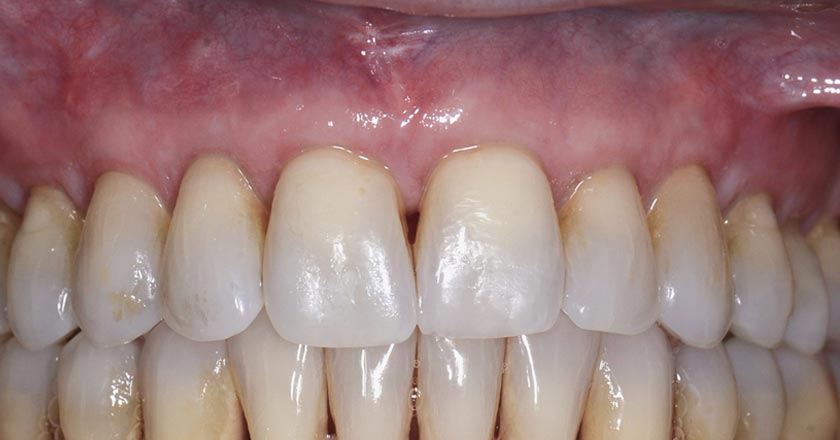

Gum Graft Upper - Before And After

Gum graft upper – before treatment

Gum graft upper – after treatment